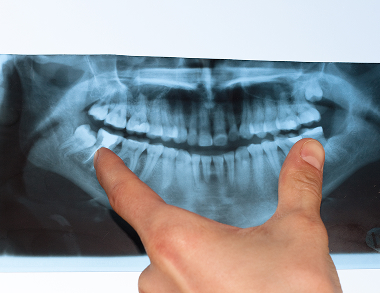

Dental X-rays are essential diagnostic images that use low levels of radiation to capture detailed pictures of your teeth, roots, and jawbone. They reveal hidden structures and problems not visible during a regular oral exam.

Common types include bitewing X-rays to check for cavities between teeth, periapical to view the entire tooth root, and panoramic images for a broad overview of the jaws, teeth, and joints.

Enhanced Image Quality

Allows for zooming and contrast adjustment to detect issues with exceptional clarity.